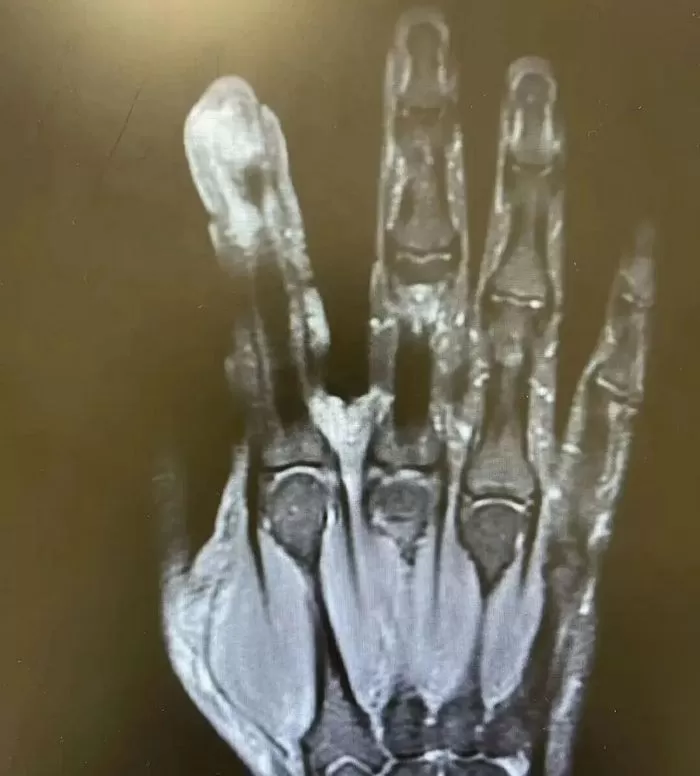

병원에 도착했을 때 리 씨의 상태는 심각했습니다. 왼쪽 검지는 무처럼 부어오르고 손가락 끝은 하얗게 변하며 궤양이 생겼고, 통증이 너무 심해 물컵조차 잡을 수 없을 정도였습니다.

검사 결과, 리 씨의 왼쪽 손가락 끝 궤양이 심하게 감염된 것으로 나타났습니다. 혐기성 연쇄상구균이 상처를 통해 뼈까지 침투하여 심각한 골수염을 유발한 상황이었습니다.

의료진은 응급 수술을 통해 괴사된 뼈 조각을 제거하고 괴사된 근육과 피부를 제거했습니다.